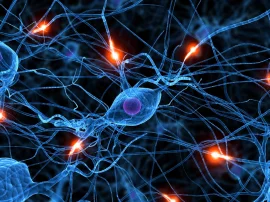

Estudo comprova que coronavírus afeta cérebro e detalha efeitos nas células nervosas

Estudo investiga como privação de sono afeta a imunidade